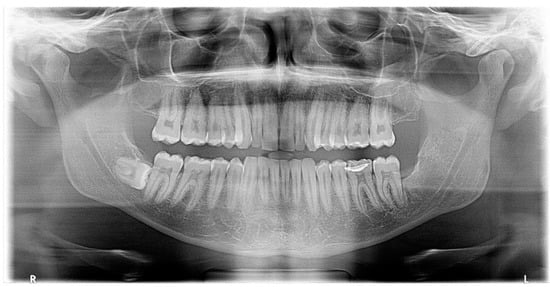

A new OPG X-ray revealed the presence of a pericoronal radiolucent lesion on an impacted tooth #48, which was inverted in the mesio-caudal direction (Figure 5). The lesion was well defined, measured 13 × 15 mm, and was surrounded by a thin sclerotic border overlapping with the distal root of tooth #47, which appeared slightly resorbed. The cyst also overlapped with the IAC, whose walls could not have been well-identified during this exam. The presumptive diagnosis was a DC.

On the complementary CBCT X-ray, it was observed an impacted tooth #48 in horizontal/inverted orientation in the mesio-caudal direction (Figure 6). The two roots were not in direct contact with the right IAC, and the tooth crown did not come into direct contact with the root of tooth #47. The pericoronal space was markedly enlarged, 13 mm wide, 17 mm high, and 15 mm long, compatible with a DC. The visible resorption of the distal root of tooth 47 made a differential diagnosis of odontogenic keratocyst less likely. The lesion was associated with an alveolar crest dehiscence of over 4 mm in length and thinned lingual cortex. The lesion displaced the IAC caudally, causing loss of visibility of its wall.